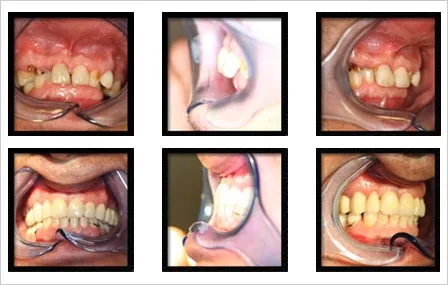

OBJECTIF

caractériser la chirurgie orthognatique pré-prothétique

>< chirurgie orthognatique classique en fin de croissance MATERIEL ET METHODE

Critères d’inclusion :

Patients adultes édentés partiels ou complet 1 ou 2 arcades

Décalage des bases osseuses ++

Réhabilitation (implanto) prothétique impossible

Classe II squelettique : 5

Classe III squelettique : 10

Hypodivergent : 6

Hyperdivergent : 4

Normodivergent : 5

Avec orthodontie : 6, chirurgie première : 9

Type de chirurgie orthognatique : Le Fort I, OSBM, Bimax, + génio

CONCLUSION

Pseudo décalage sagittaux >> greffes d’apposition osseuse

CI III préexistante >> greffes osseuses + chirurgie orthognatique

Permet une réhabilitation prothétique optimale + confort de vie pour CI II ± perte de DVO

CI III constitutionnelle